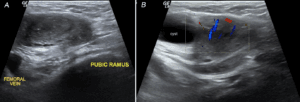

At this point, the admitting medicine team was considering an infectious or inflammatory etiology and believed the palpable lesion in the left groin to be secondary to lymphadenopathy rather than an inguinal hernia as the patient believed. A point-of-care ultrasound examination was performed to visualize the enlarged lymph nodes. Surprisingly, a large echogenic thrombus was seen extending from the common femoral vein (CFV) to the mid-thigh. The CFV and femoral vein (FV) were distended and non-compressible (Figure 1, Video S1).

Figure 1. (A) A distended left Common Femoral Vein seen on point-of-care ultrasound (POCUS). (B) The same vein proves to be non-compressible when pressure was applied.

Video S1. A distended, non-compressible left CFV and FV seen on point-of-care ultrasound.